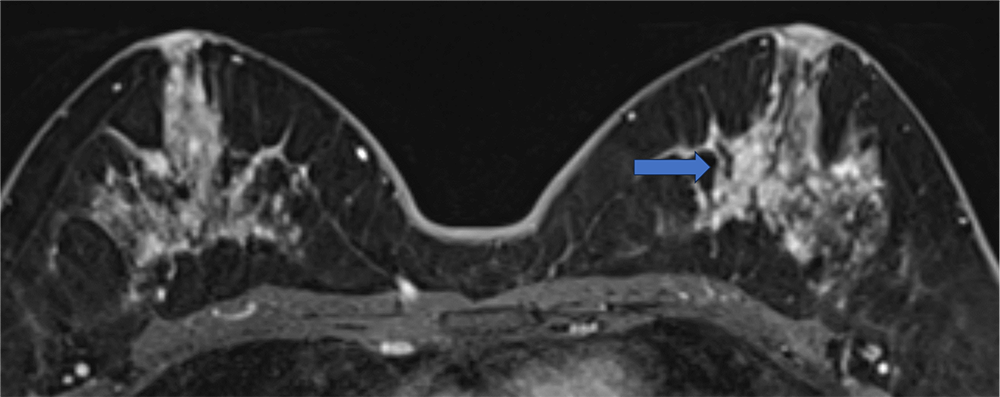

5. Ultrafast DCE 造影剤投与約20秒後、23秒後、26秒後

BPEが目立たないため、左乳房内側の病変が容易に同定できる